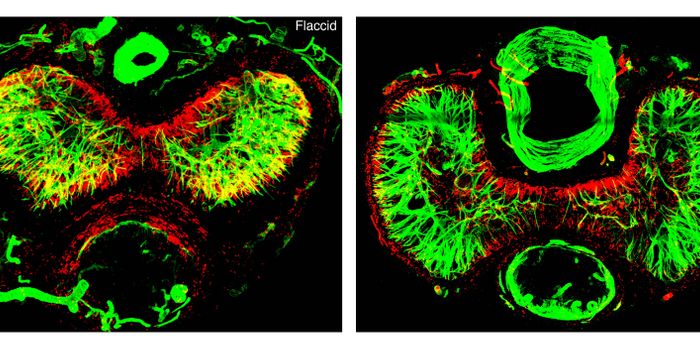

SEP 02, 2024Genetics & GenomicsWith powerful tools that sequence the genes that are being expressed in individual cells, scientists have gained new ins ...